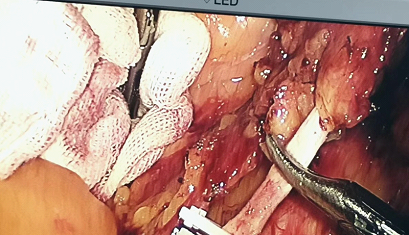

▲手术操作中

腹腔镜NOSES术,即经自然腔道(直肠或阴道)取标本手术(natural orifice specimenextraction surgery,NOSES),是使用腹腔镜器械、TEM或软质内镜等设备完成腹腔内手术操作,经自然腔道(直肠或阴道)取标本的腹壁无辅助切口手术。NOSES术为微创手术,其优势包括避免腹壁辅助切口,减轻患者术后疼痛,保留腹壁功能,具有美容效果等。腹腔镜NOSES术和常规的腔镜手术最大的区别就在于消化道重建方式和标本的取出途径,避免了腹壁取标本的辅助切口,术后腹壁仅存留几处小的戳卡疤痕。